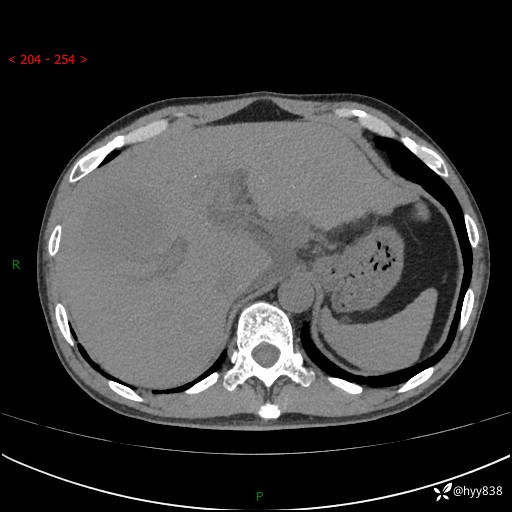

上腹部CT平扫+增强(两期)